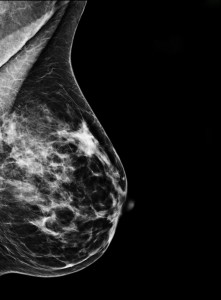

Mammograms are not fun. The atmosphere of the screening office is often hectic, somber and noisy. Not a good combo when one is back to see if your breast cancer may have come back or that “calcification” in the same breast that you had breast cancer in over 5 years ago, maybe turning into something. I never think it has. I always have the mantrs, just like when I get on a plane. I’m on this plane and I’m supposed to live, so it won’t be crashing. The probelm with my supre optimistic view of my health is that yea, I did have cancer and mostly it doesn’t haunt me. Only if I’m reminded by the medical profession that I must be careful not to forget… that I had cancer and therefore… therefore what? That I might get it again? How does that serve me? I could get hit by a bus, but I’m still crossing this street.

An essay I wrote, I Almost Forgot I had Breast Cancer…